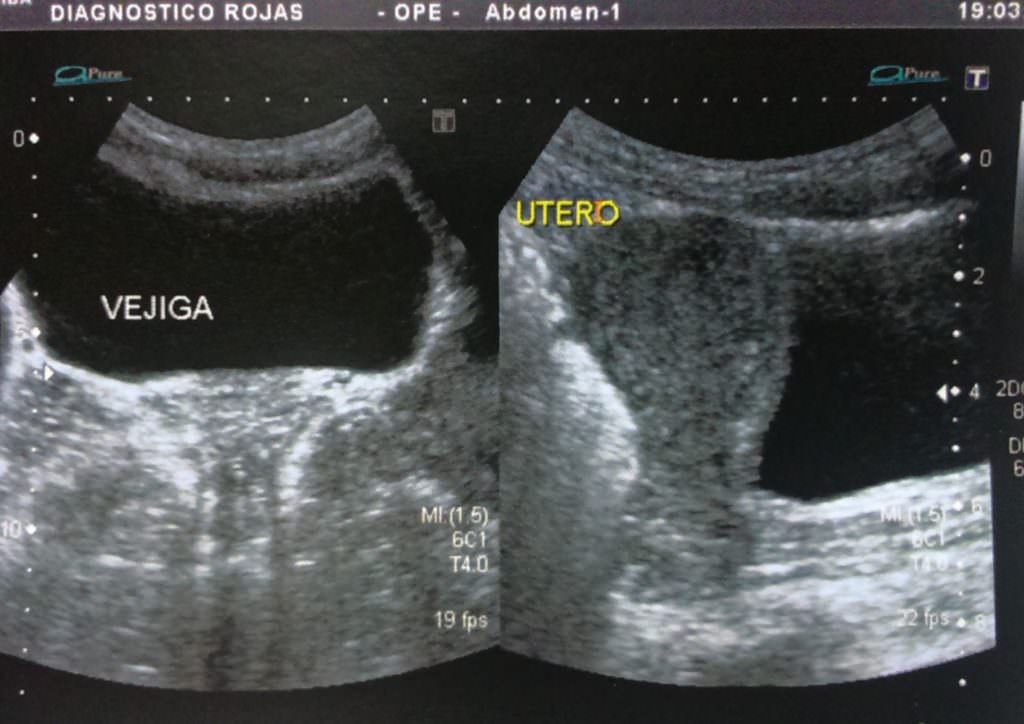

Aplicaciones en obstetricia y ginecología:.

que es una ultrasonografia La ultrasonografía eus ofrece una imagen. La denominación ecografía o ultrasonido se refiere a un procedimiento que emplea ondas sonoras de alta frecuencia para ver el interior del cuerpo, colocando un transductor o. Una ecografía, también conocida como sonograma, es una prueba de diagnóstico por imagen que utiliza ondas sonoras (ultrasonido) para crear imágenes de órganos,. La ultrasonografía es un método de diagnóstico por imagen que utiliza un transductor para emitir. Un ultrasonido de la mama es una técnica de imágenes que se utiliza comúnmente para detectar tumores y otras anomalías en los senos. Aplicaciones en obstetricia y ginecología:. El ultrasonido es un examen médico no invasivo que ayuda a los médicos a diagnosticar y tratar condiciones médicas. Descubre qué es un ultrasonido o ecografía y cuáles son sus usos en el cuidado de la salud.

Prácticas para un Examen de Ultrasonografía